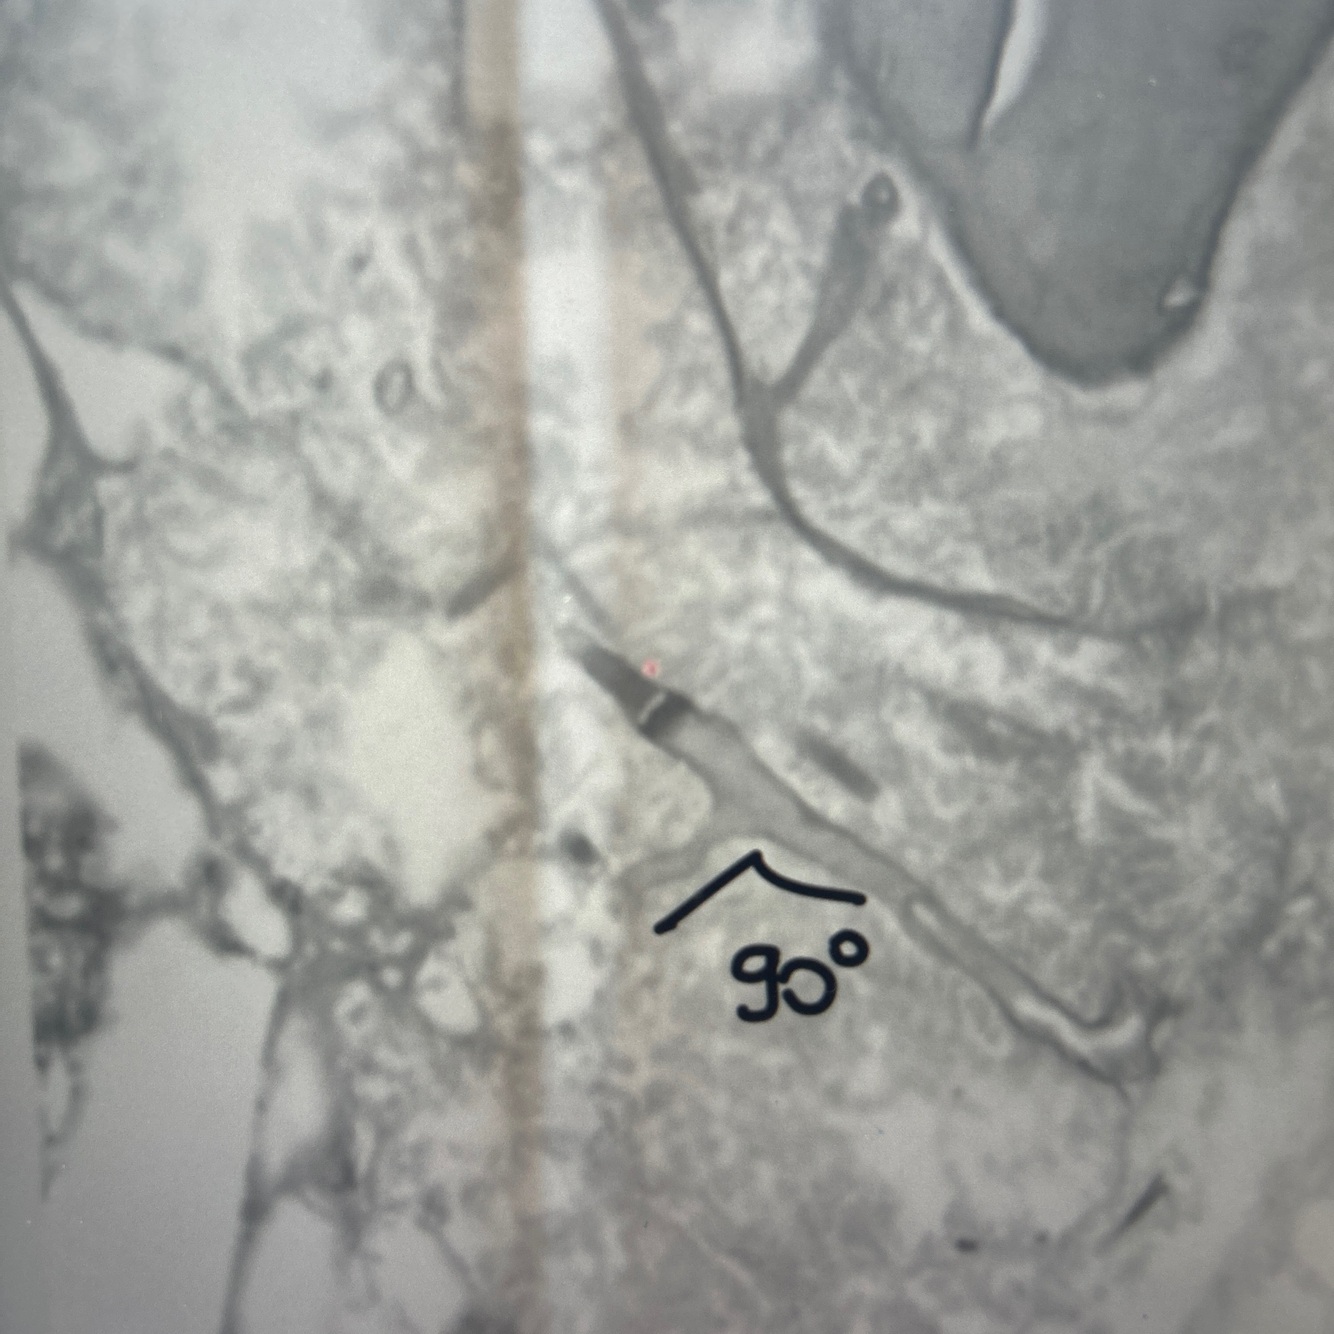

Qual achado da imagem no círculo ? Diagnóstico?

Leveduras agrupadas e em aspecto catenular

Infiltrado granulomatoso

Lobomicose